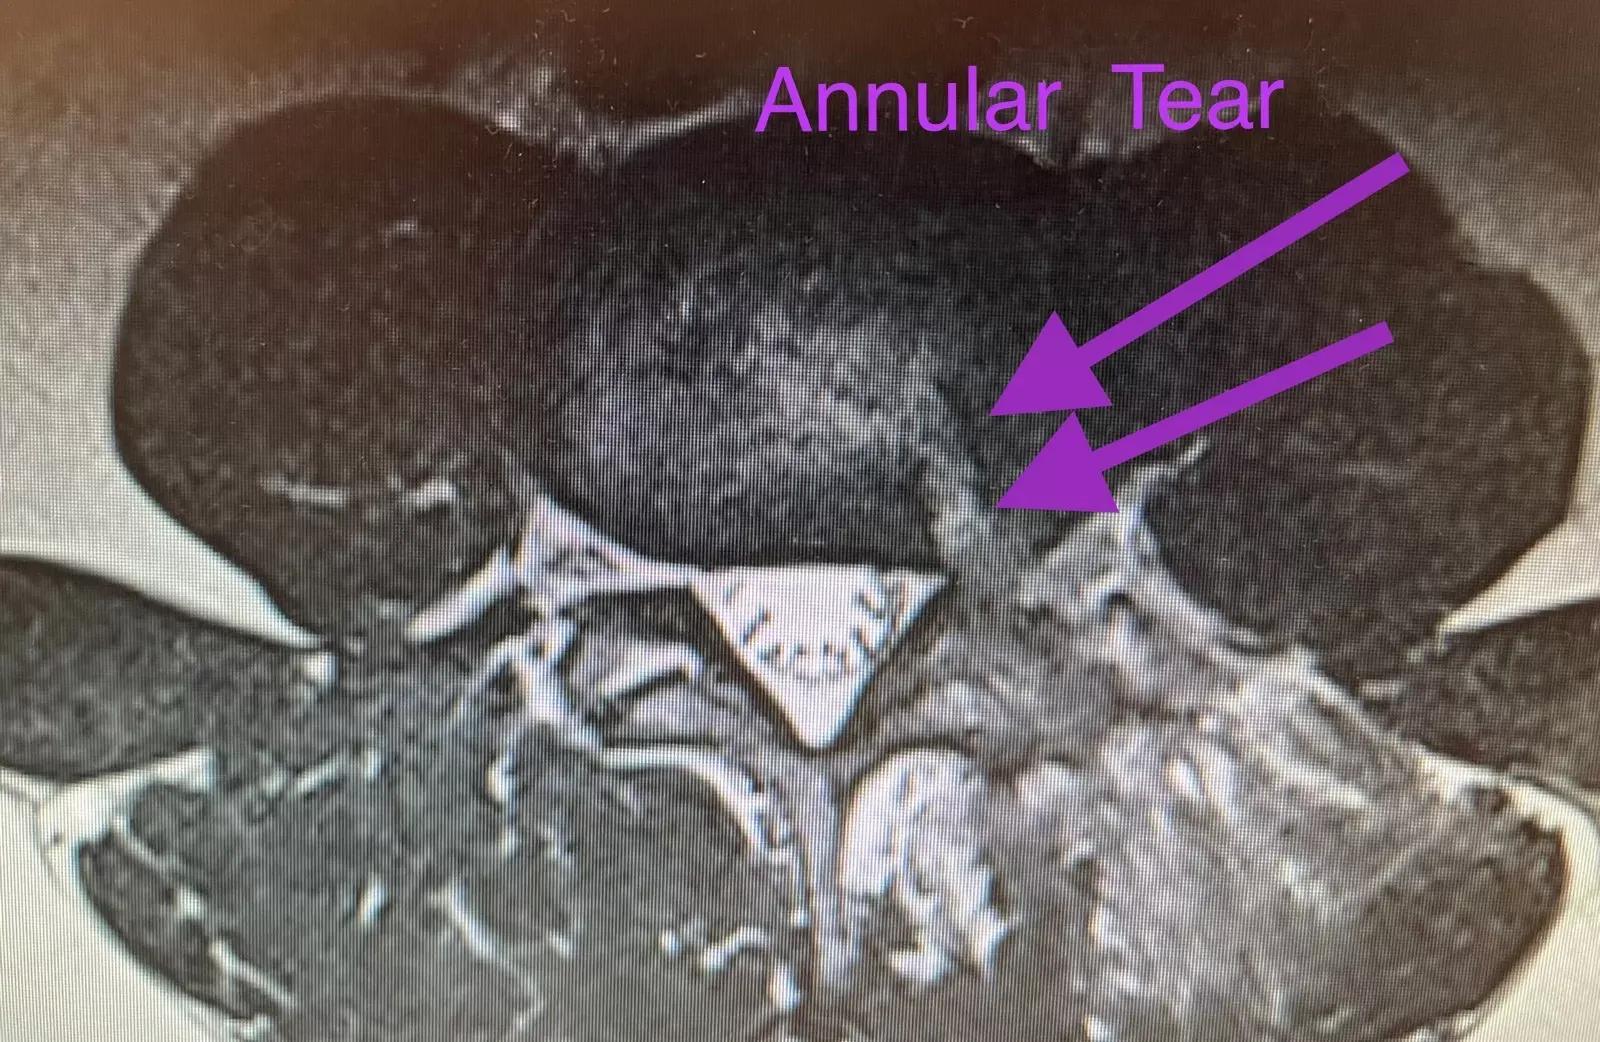

Bulging Disc Treatment Explained: Symptoms, Causes, and Solutions

The Deuk Spine blog is dedicated to providing education and information on the root cause causes of back and neck pain, treatment solutions, industry insights, and the alternatives to spinal fusion surgery including our proprietary Deuk Laser Disc Repair.